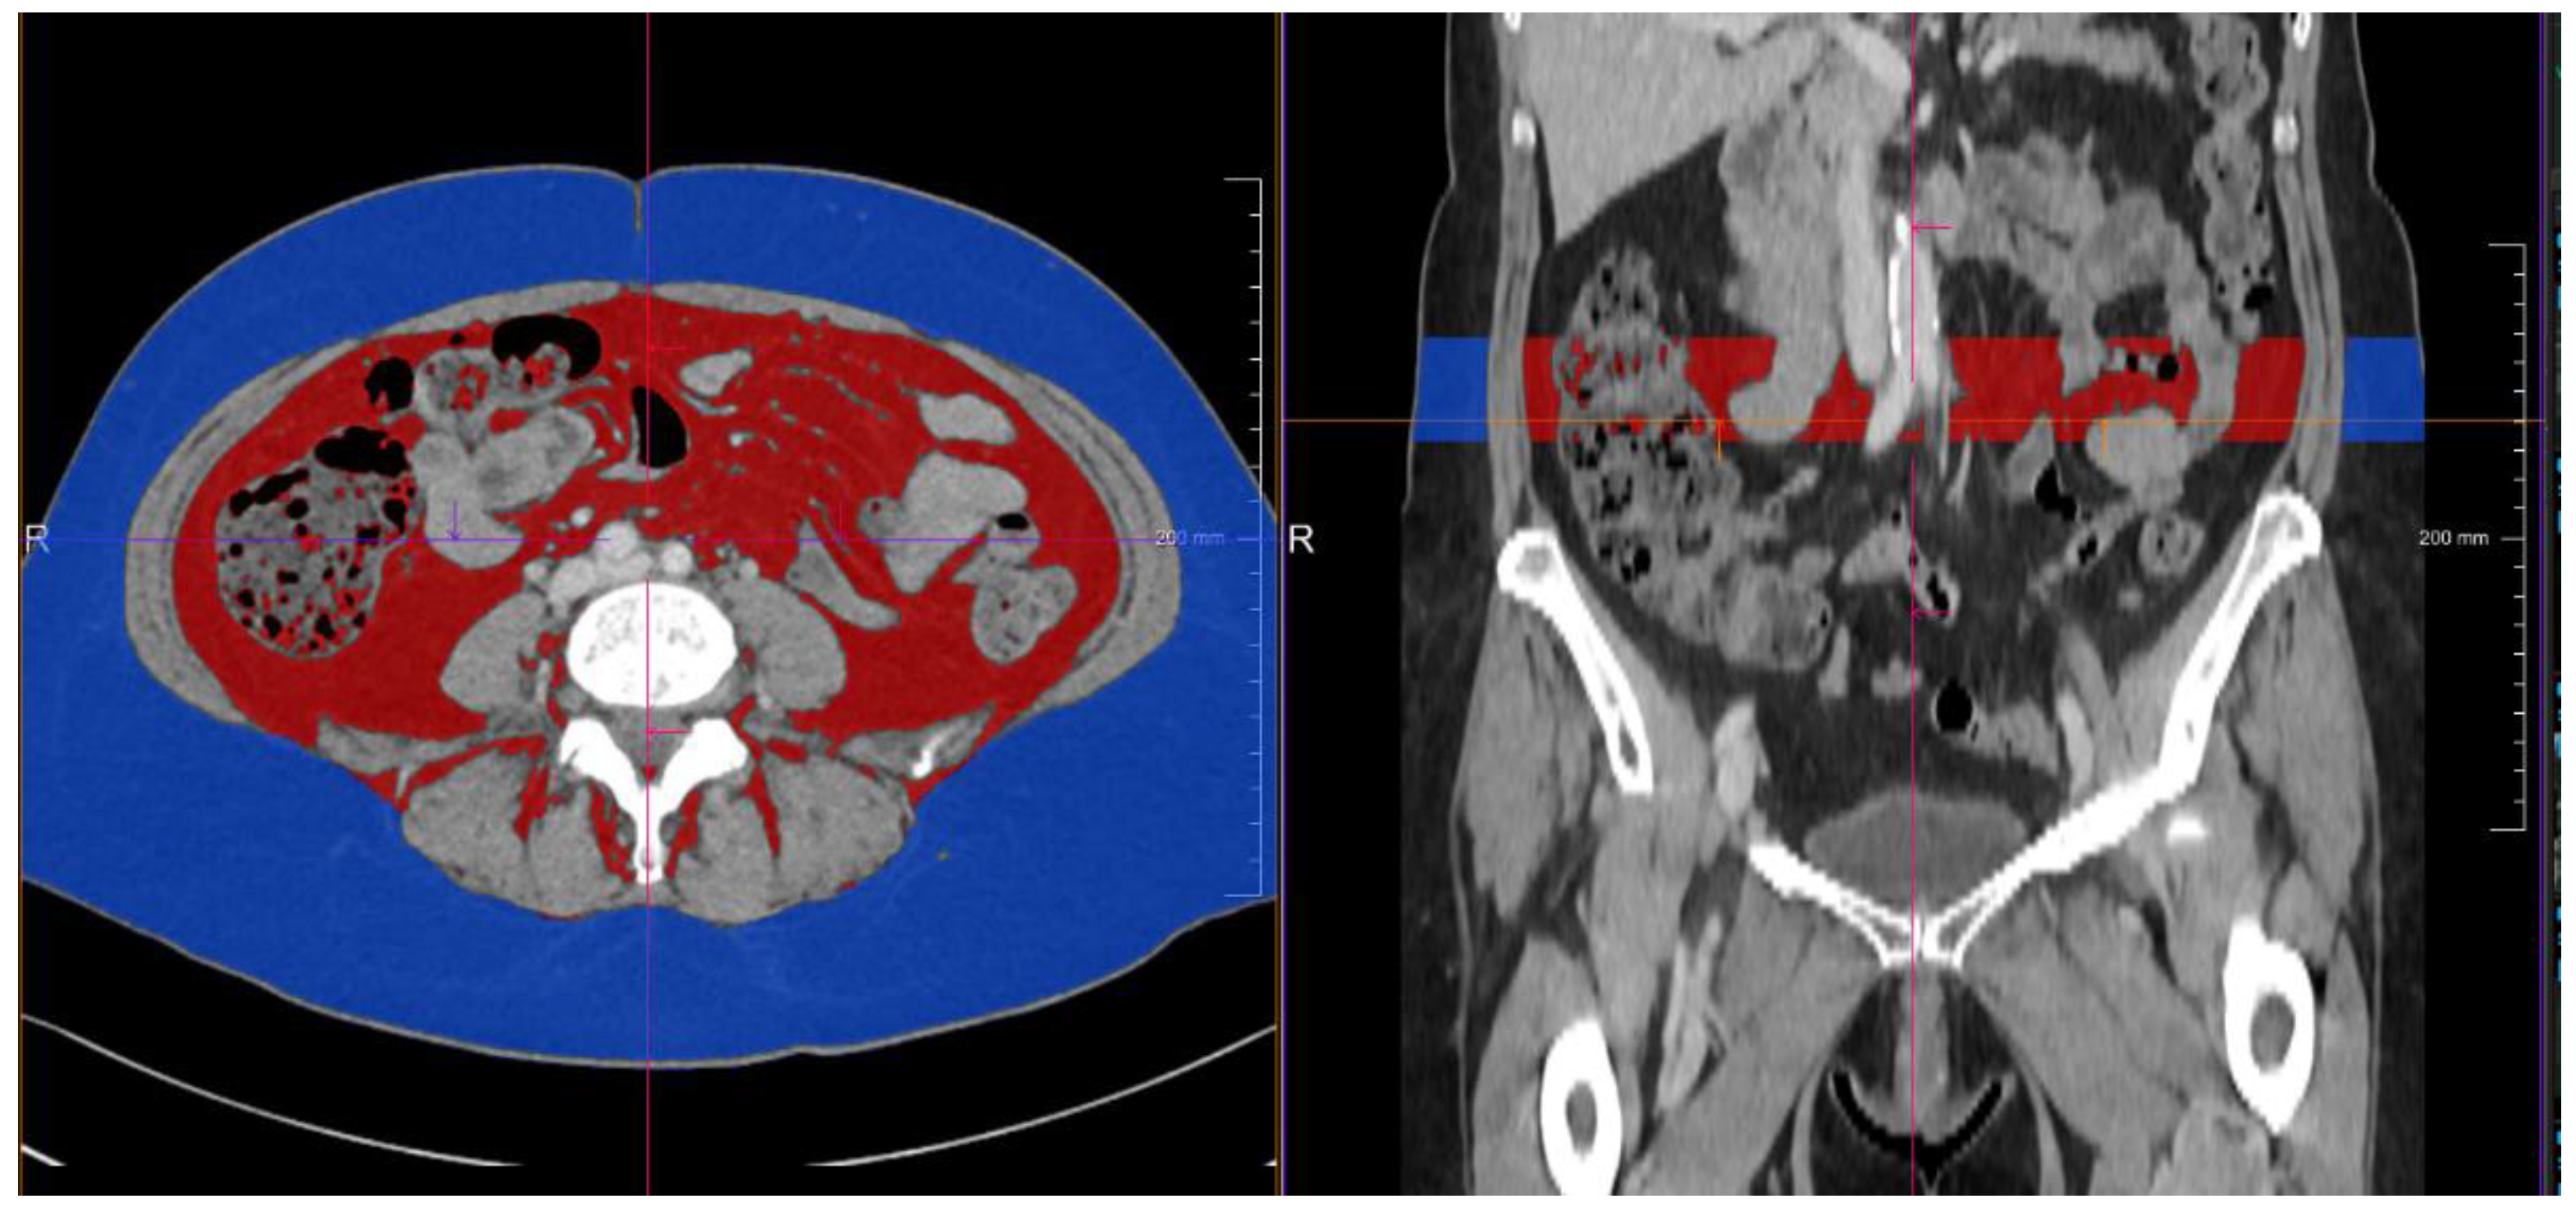

3.2. Predictive Value of a Pretherapeutic BMI for CPI Therapy

| CT-derived subcutaneous fat volume (mL) | 711.8 (334.8–1202.3) | 476.7 (223.0–721.7) | 1242.9 (904.6–1534.1) | <0.001 * |

| CT-based visceral fat volume (mL) | 327.1 (160.1–557.2) | 226.3 (99.5–388.7) | 532.4 (285.2–755.4) | <0.001 * |

| overall response rate (ORR) | 36.1% (13/36) | 5.0% (1/20) | 75.0% (12/16) | <0.001 * |

| disease control rate (DCR) | 58.3% (21/36) | 40.0% (8/20) | 81.3% (13/16) | 0.023 * |